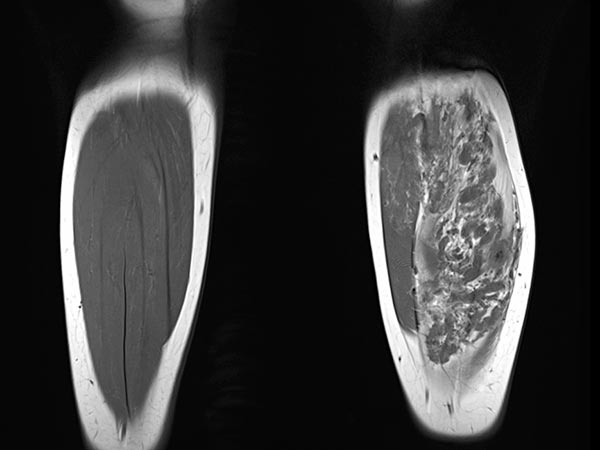

In der axialen T2-gewichteten MRT des linken Unterschenkels finden sich mehrere dilatierte, dysplastische Venen im Sinne einer venösen Malformation in der gesamten oberflächlichen Flexorenmuskulatur. Durch den niedrigen Durchfluss kommt es zur Stase des Blutes innerhalb der Malformation mit der Bildung von Flüssigkeits-Spiegeln. Praktisch der gesamte Muskel ist von Malformation und Fettgewebe durchsetzt. Großer Thrombus in einer dilatierten, dysplastischen Vene.

In der koronaren nativen T1-gewichteten Kontroll-MRT sind die Gefäßanteile der Läsion deutlich weniger abgrenzbar. Es bleibt jedoch deutlich zusätzliches Gewebe bestehen („Salz-und-Pfeffer-Muster“), zum Teil hyperintenses Fettgewebe, zum Teil hypointenses Bindegewebe. Dies ist typisch für eine Fibro-adipose Vascular Anomaly (FAVA).

Auch in der axialen Kontroll-MRT in T2-Wichtung sind die Gefäßkanäle zum großen Teil verschlossen. Nach erfolgreichem Verschluss bleibt aber ein schwarz-weißes „Salz-und-Pfeffer-Muster“ bestehen, das typisch für eine FAVA ist. Es besteht aus Fettgewebe (hyperintens) und Bindegewebe (hypointens).